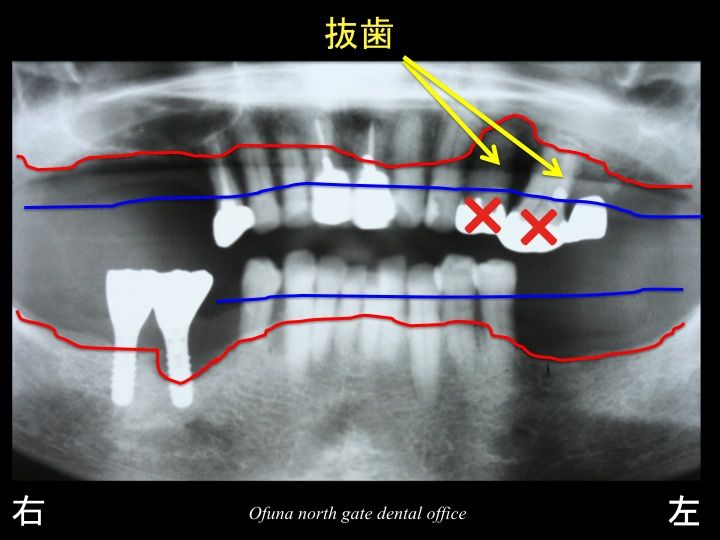

上顎左側の奥歯に関しては グラグラ です。

上顎左側の奥歯 2歯は保存が難しい状態でした。

抜歯と判断しました。

他の歯もかなり 歯周病が進行していました。

このままでいると ほとんどの歯はダメ(抜歯)になってしまうような状態です。

それでは、これも先程と同じように

骨吸収の状態を線で書いてみましょう!

青線が骨吸収を起こす前の骨の位置です。

赤線は、現在の骨の位置です。

骨吸収が非常に進行しているのが分かると思います。